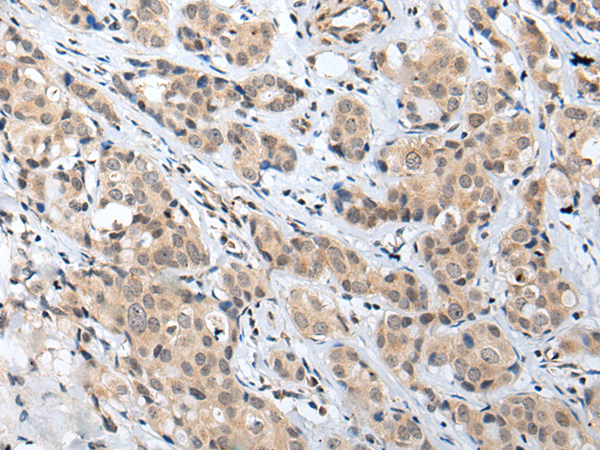

IHC positive control: |

Human lung cancer and human breast cancer |

IHC Recommend dilution: |

25-100 |